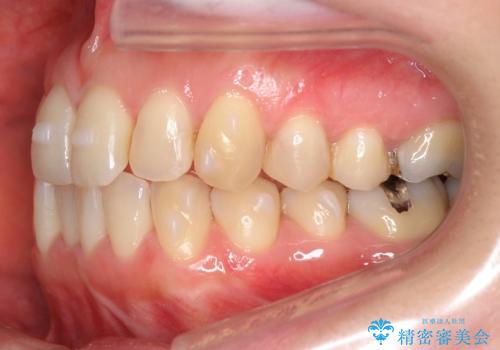

上の前歯が一部引っ込んでいる 下のがたがた マウスピース矯正

- 前歯2本が後ろに引っ込んでいる状態でした。

マウスピースで歯を抜かずに矯正しました。

かみしめがある方は、奥歯のかみ合わせが弱くなることがマウスピース矯正の欠点ですが、装着時間や時間帯を工夫して奥歯もしっかりかんだ状態で矯正終了をしています。

左上4番は、虫歯治療をして、セラミッククラウンで修復しています。